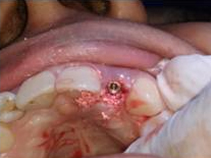

Placement of Implant

Single Tooth Implant